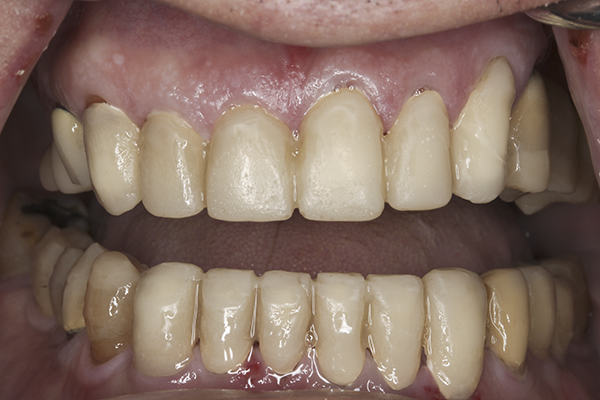

(24.) Provisionals, anterior, closed view.

Figure 24

(21.) Provisionals, anterior, open view. Note the composite tops on the posterior teeth and improved planes of occlusion.

Figure 21

Based on examination of the mounted models, it was decided to treat the patient in centric relation and an additive equilibration approach was used to idealize the planes of occlusion. On the articulator, the patient’s first point of contact in centric relation was the starting point and an additive equilibration technique was implemented, building the teeth to meet ideally at the patient’s first point of contact. A diagnostic wax-up was completed on the mounted models to determine where the anterior and posterior teeth needed to be in space. A template from the wax-up was used to fabricate the anterior provisional restorations. The anterior teeth were restored with full-coverage restorations, creating ideal stops between the lower incisal edges and upper cingulums. The maxillary incisal edges were placed to provide proper phonetics and an acceptable esthetic outcome, while still working within the envelope of function. All of these parameters are worked out in the provisionals prior to moving forward with definitive restorations. With the anterior provisionals in place, posterior composite tops were bonded to his existing dentition, creating ideal centric stops on the posterior teeth. The anterior and canine guidance was developed, resulting in immediate separation of the posterior teeth during all excursive movements (Figure 17 through Figure 28). Once the author and patient were happy with the function, esthetics, phonetics, and comfort of the provisionals, an impression of the approved provisionals was taken and sent to the laboratory to use as a guide in the fabrication of the final anterior crowns. With the final restorations delivered, the patient was extremely happy with his new smile. Most importantly, proper anterior and canine guidance in harmony with his envelope of function was achieved, which resulted in comfortable function and immediate separation of the posterior teeth during protrusive and lateral excursions (Figure 29 through Figure 42).